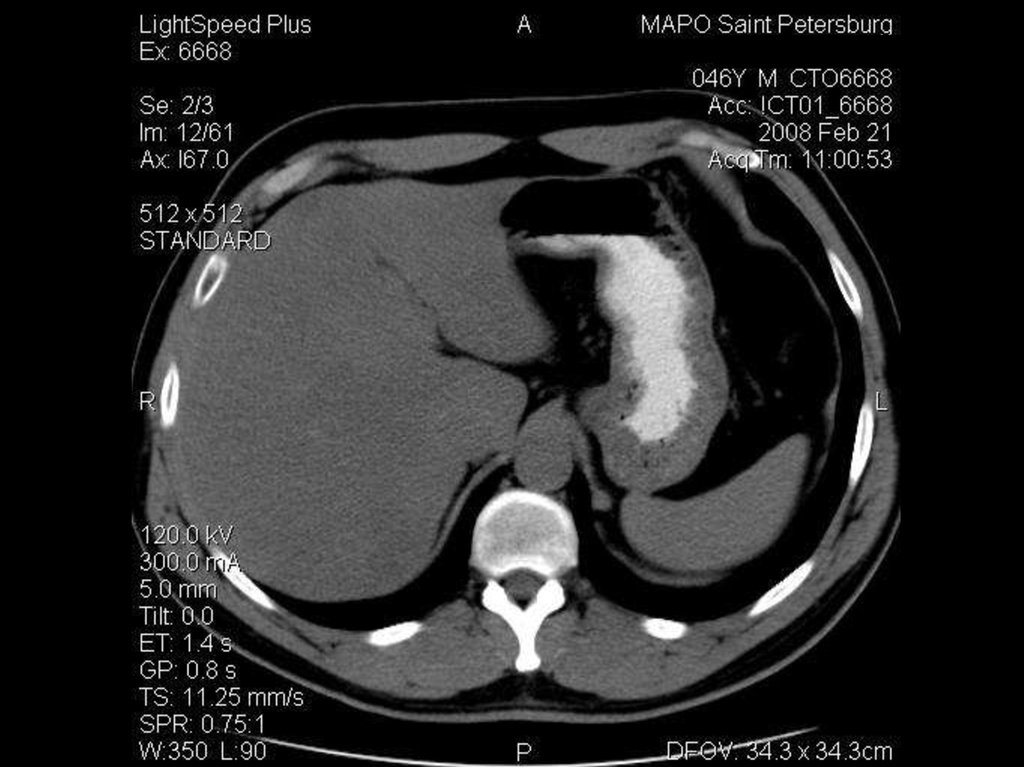

исследование брюшной полости

Ток: 300 мА

Напряжение: 120кВ

Толщина среза: 5.0 мм

Матрица: 512х512

Режим: спиральный, 11.25 мм/с